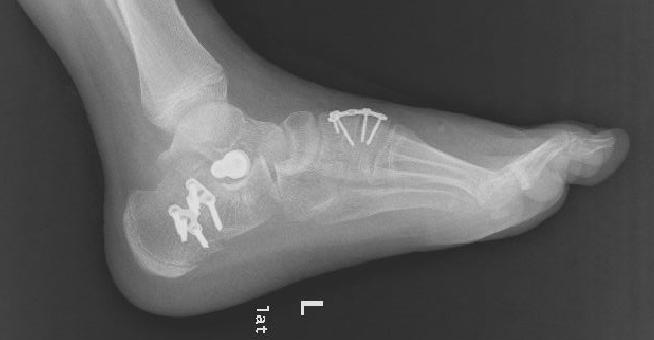

上图为患者扁平足术后影像资料

根据病情,小儿骨科积极邀请昆明医科大学第二附属医院骨科足踝专家进行会诊及手术指导。经医院小儿骨科和昆明医科大学第二附属医院骨科足踝专家的配合,对该复杂僵硬性扁平足患者进行了左侧扁平足跟骨内移截骨钢板固定,距下关节制动器置入,副舟骨切除,胫后肌腱止点重建术,腓长肌松解,内侧楔骨截骨植骨钢板固定,取同侧髂骨植骨术等多处复杂性手术治疗,手术历经2小时,圆满顺利完成。